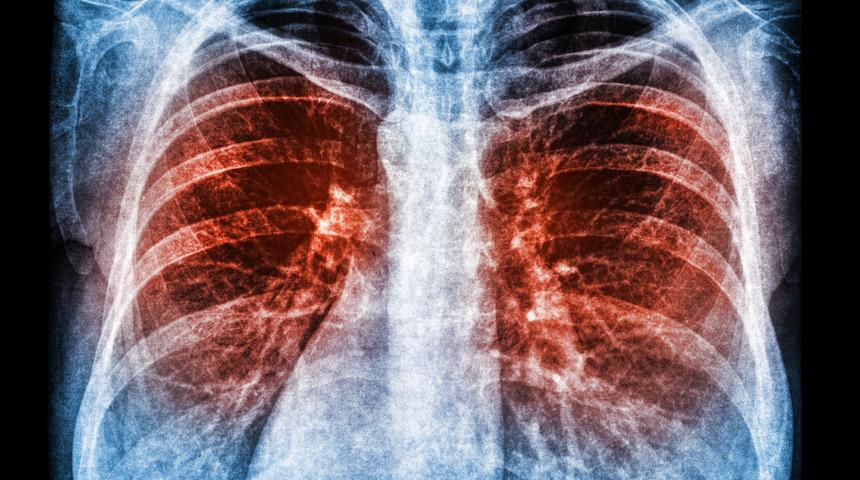

Tespit edilen protein, koronavirüsün S-proteini ile temasa geçerek içine girebilip onu içten yok edebiliyor. Bu protein temelinde geliştirilen ilacın fareler ve hamsterler üzerinde yapılan testlerde etkisini gösterdiği belirtildi.

Pittsburgh Üniversitesi’nde bir grup bilim insanı, Kovid-19 hastalığına yol açan SARS-CoV-2 virüsünü az dozda bile tamamen yok edebilen bir protein keşfetti. İlgili araştırma, Cell bilim dergisinde yayınlandı.

Kovid-19’a kaşı geliştirilen Ab8 ilacının üretiminde kullanılan tam uzunluktaki antikordan 10 kat daha küçük olduğu ifade edilen bu protein bileşiği, koronavirüsün S-proteini ile temasa geçme yeteneğine sahip 100 milyar potansiyel molekülün hızlı analizi sırasında keşfedildi. Patojenin de vücuda tam olarak bu madde aracılığıyla nüfuz edebildiği kaydedildi.

Yazıda, bu maddenin fare ve hamsterlarda koronavirüs önleme ve tedavisinde oldukça etkili olduğu gösterdiği aktarılırken uzmanlar, tespit ettikleri proteinin dokularda yayılma yeteneğine sahip olduğu, bu yüzden virüsü etkisiz hale getirme konusunda çok başarılı olduğu sonucuna vardı.

Aynı zamanda söz konusu moleküllerin insan hücreleriyle etkileşime geçmediği, bu sayede yan etki olasılığının çok düşük olduğu kaydedildi.